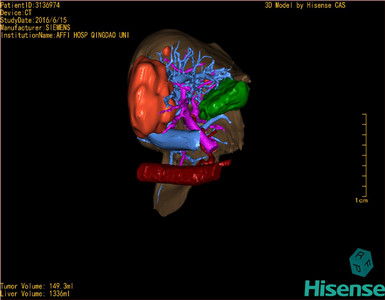

通过调节窗宽窗位调整CT序号,对肿瘤,肝实质,胆囊,下腔静脉,肿瘤,肝动脉、门静脉及肝静脉等进行三维重建;系统自动计算肿瘤体积和肝脏体积。

模拟手术操作,自动计算切除肿瘤体积。肝脏体积为1336ml,肿瘤体积为149.3ml,肿瘤体积为肝脏体积的11.2%,通过比对50-60岁正常肝脏体积为1330.41±329.13 ml,通过术前模拟手术,精准判断切除后剩余肝脏体积能耐受,避免肝衰竭发生。

术前三维重建:重建图片

重建视频